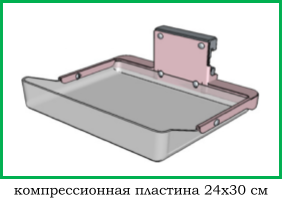

Шаг 3. Формат приемника рентгеновского изображения

В маммографии существует два общепринятых формата приемника рентгеновского изображения: 18х24 см и 24х30 см. На приемнике 18х24 см одномоментно (за одну экспозиции, без дополнительной укладки) можно исследовать грудь приблизительно до 2 размера включительно, а на приемнике 24х30 см - до 5 размера включительно.

Маммографы, рассчитанные на работу с приемников 18х24 см, стоят дешевле своих аналогов 24х30 см, однако маммографы с приемником 24х30 см являются более универсальными в своем применении.

Следует отметить, что исследование молочной железы большего размера, чем формат приемника, осуществляется в несколько экспозиций, что приводит к увеличению лучевой нагрузки на пациента, повышению общего времени обследования, повышению дискомфорта пациента, вызванного многократной компрессией органа, кроме этого, усложняется анализ серии рентгенограмм врачом рентгенологам.

Простой пример: во время скринингового обследования исследуют обе молочные железы в двух проекция (прямой и косой), если молочная железа целиком помещается на приемник, то делают четыре снимка, если молочную железу приходится снимать в два этапа, то делают уже 8 снимков.

Подавляющее большинство маммографов комплектуются приемниками 24х30 см.

Компрессионные пластины различных форматов